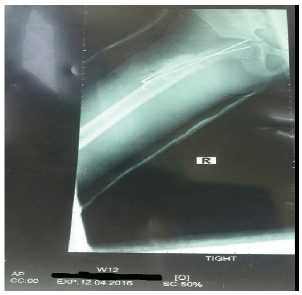

Figure 2:X-ray showing displaced cervicotrochanteric fracture of the right femur day 10.

This occurred in the 8-year-old boy who had his falling school wall landing on the right thigh whilst playing at school (Figure 2). He had closed reduction and percutaneous pinning with 2 cannulated screws without hip spica. Child was doing well post operatively on the ward until day 10 when he suddenly sat upright in a chair to receive lessons from the school teacher. He was in sudden excruciating pain and subsequent repeated radiograph confirmed the cut out of the cannulated screws (Figure 1). He later had closed reduction and percutaneous pinning with 22mm-Kirschner wire and No. 5 TiCron tension band as well as hip spica applied after previous screws removed (Figure 3 & 4).